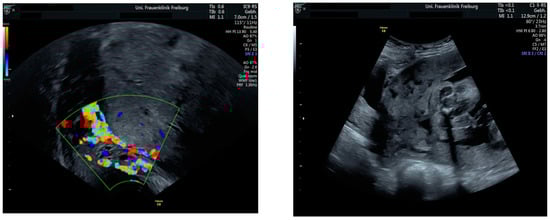

Sonographic findings (Figure 9):

Figure 9.

Irregular, large lacunae within the placenta, Hypervascularity, Turbulent flow inside the lacunae Diameter gaps.